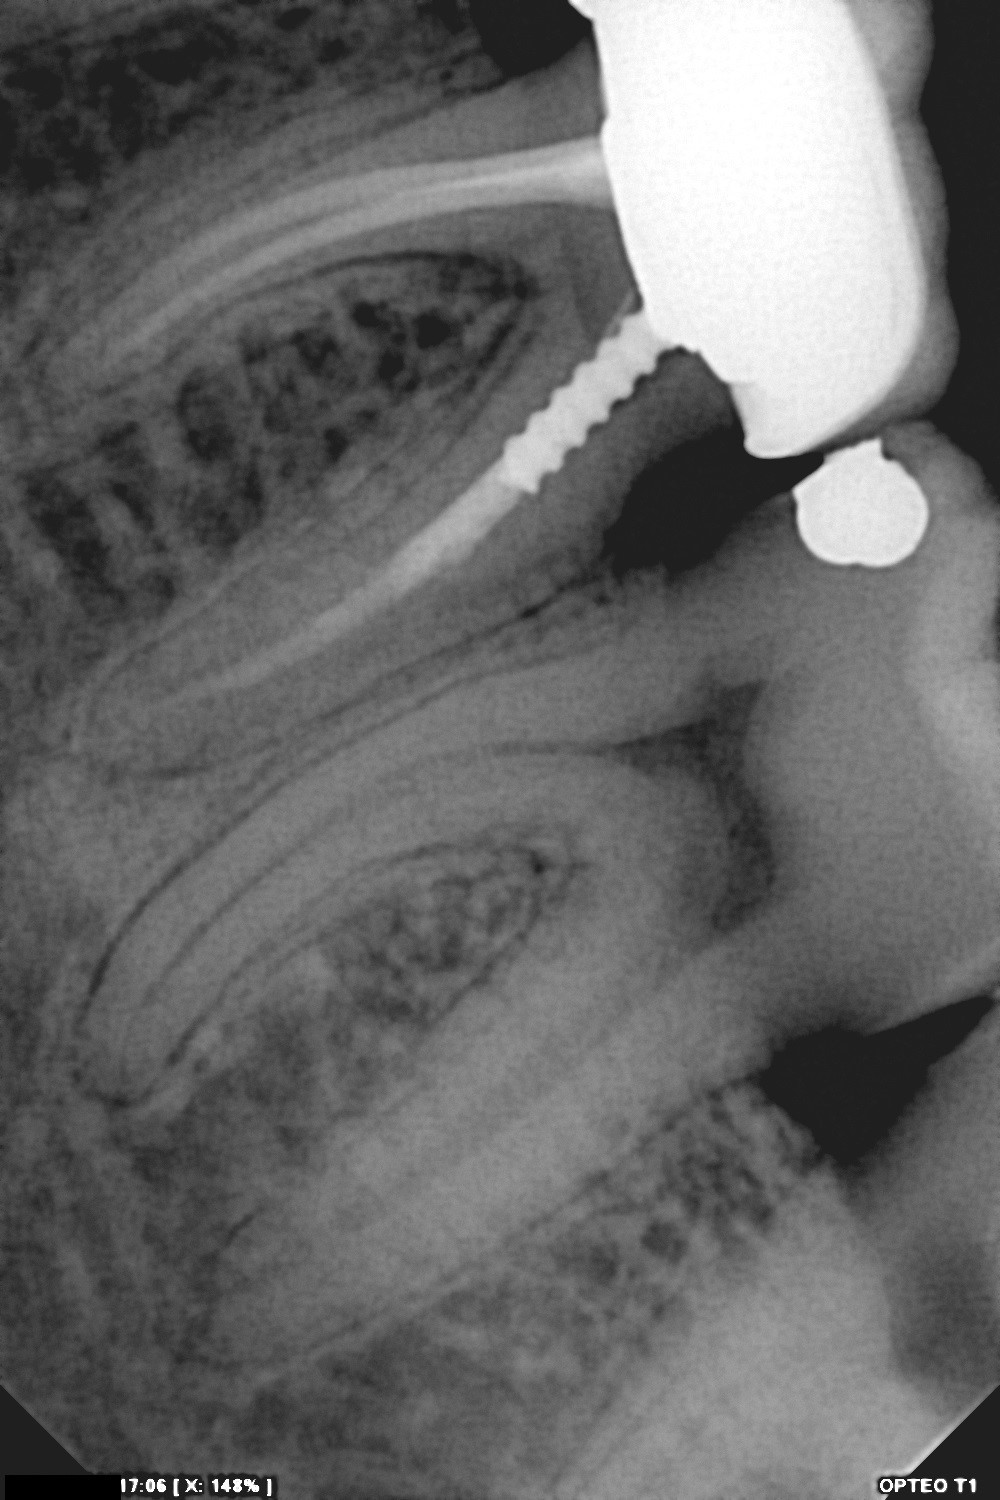

سنسور رادیوگرافی تک دندان مدل OPTEO

سنسور رادیوگرافی دیجیتال دندان مدل Opteo

سنسور ديجيتال راديوگرافي دندان مدل Opteo T1

سایز سنسور بسیار مناسب و طراحی بی نظیر

لبه های رند برای پوزیشن دهی بسیار راحت

امکان چرخش 360 درجه ای کابل دایرکت USB که در گردنه ی سنسور تقویت شده است